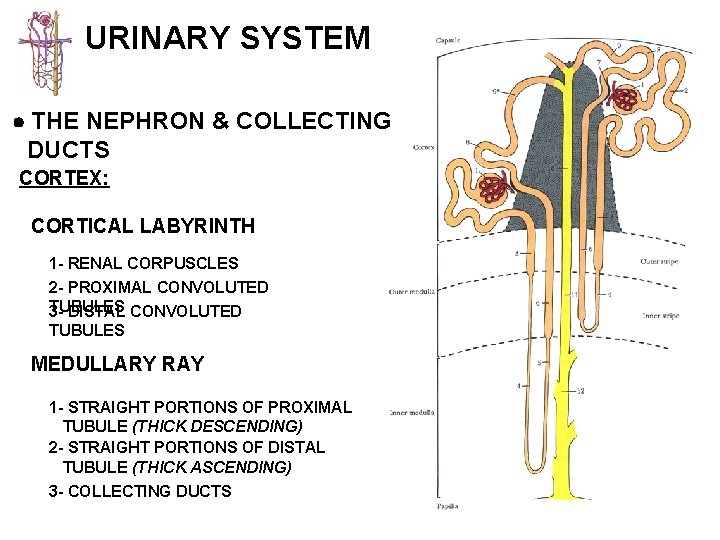

URINARY SYSTEM THE NEPHRON & COLLECTING DUCTS CORTEX: CORTICAL LABYRINTH 1 - RENAL CORPUSCLES 2 - PROXIMAL CONVOLUTED TUBULES 3 - DISTAL CONVOLUTED TUBULES MEDULLARY RAY 1 - STRAIGHT PORTIONS OF PROXIMAL TUBULE (THICK DESCENDING) 2 - STRAIGHT PORTIONS OF DISTAL TUBULE (THICK ASCENDING) 3 - COLLECTING DUCTS